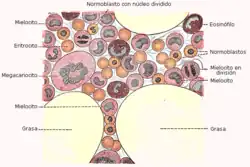

Hematopoyesis

- Hematopoyesis: La médula ósea roja, que se encuentra en el tejido esponjoso de los huesos largos encargada de la formación de las células sanguíneas.

Médula ósea

Se llama médula ósea a un tipo de tejido blando que se encuentra en el interior de los huesos. Por término medio, representa alrededor del 4 % del peso total de un adulto humano, por lo tanto una persona de 65 kg cuenta con 2.6 kg de este tejido.[17] Pueden diferenciarse dos tipos: médula ósea roja y médula ósea amarilla.

- Médula ósea roja. En ella se fabrican las células que pasan a formar parte de la sangre, por lo que recibe el nombre de tejido hematopoyético. En un adulto humano se localiza principalmente en el esternón, costillas, cráneo, columna vertebral, pelvis, escápula y los extremos o epífisis de los huesos largos. Tiene una función crucial pues genera los hematíes que transportan el oxígeno a las células, los glóbulos blancos o leucocitos que permiten combatir los procesos infecciosos y las plaquetas que hacen que se coagule la sangre cuando se produce la rotura de algún vaso sanguíneo. Si la médula ósea roja no cumple su función se produce una situación muy grave que hace peligrar la vida.[1][2] Está constituida por un 60 % de células hematopoyéticas y un 40 % de adipocitos. Su composición aproximada es 40 % de grasa, 40 % de agua y 20 % de proteínas. Produce cientos de millones de células por día que se incorporan a la sangre mediante los vasos capilares que la atraviesan.[18]

- Médula ósea amarilla. Está formada principalmente por grasa y no participa apenas en la hematopoyesis. Se localiza en la cavidad medular situada en la porción central o diáfisis de los huesos largos.[1][2] El 95 % de su peso son adipocitos y solo un 5 % son células hematopoyéticas. La composición aproximada es 80 % de grasa, 15 % de agua y 5 % de proteínas.